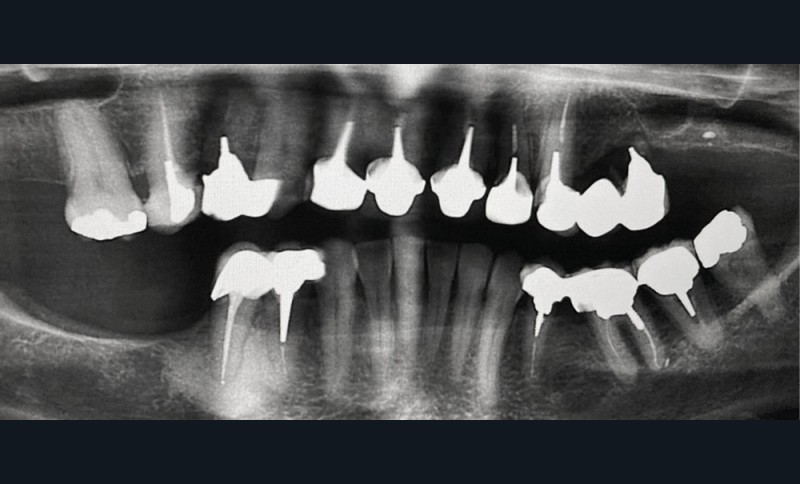

Contexte malin

Un examen clinique attentif prenant en compte les facteurs de risques carieux et parodontaux (contrôle de plaque, tabagisme en particulier) sera réalisé. Un bilan radiographique de première intention sera également nécessaire. A minima, la radio panoramique est indispensable. Elle sera complétée éventuellement par des clichés rétro-alvéolaires. En cas de doute, sur un foyer infectieux chronique péri-apical notamment, ces examens devront être complétés par un bilan d’imagerie tridimensionnel de type scanner ou CBCT. Les lésions de ce type, dans les régions sous-sinusiennes en particulier, sont difficiles d’accès à l’imagerie standard (fig. 1).